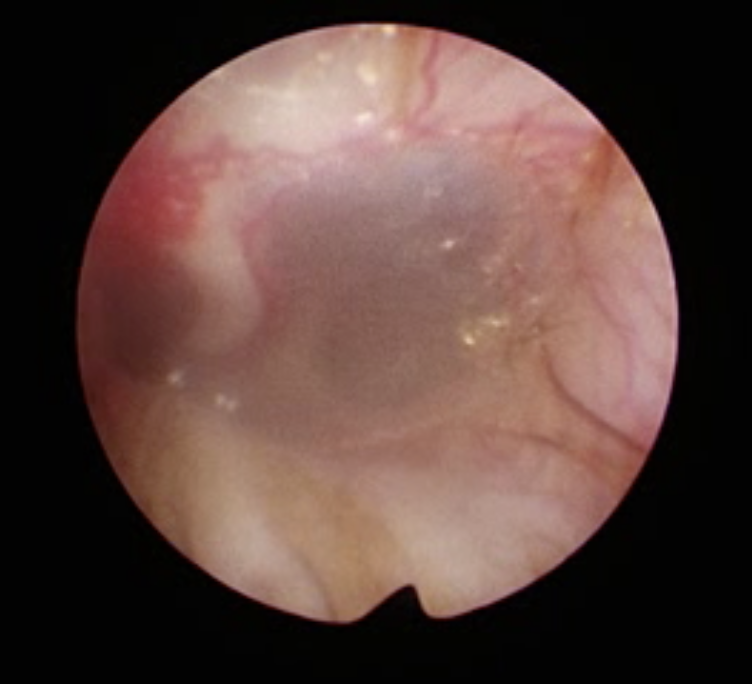

鎮静下で見せてもらうと草の実などの異物や腫瘍などはなく毛が鼓膜に刺さったり触れています。 実はこの毛による鼓膜への刺激というのは意外と多いのです。急に発症する子や慢性経過の子もいます。

先ほどのPSPP分類ではこの毛は「主因」となります。これを放置していると細菌やマラセチアの増殖に繋がり一気に悪化して所謂「耳漏」などを起こします。

柴犬などは耳周りの硬い毛が耳道内に落ちていき束になっている子もよく見かけます。

この毛は「落毛」などと言われこれによる鼓膜刺激を刺毛性鼓膜炎などと言われたりします。

治療はこの毛を丁寧に取り除くことになります。

昔はたった1本の毛でそんな症状出る?とか、本当にこれが原因?と思っていましたが、実際に取り除くと翌日から症状が消失します。